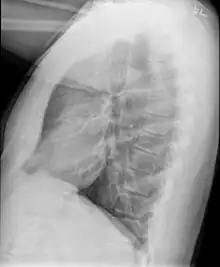

Medical imaging

Early in the disease chest radiography is typically normal but may show hyperinflation.[6] As the disease progresses a reticular pattern with thickening of airway walls may be present.[4][6] HRCT can also show air trapping when the person being scanned breathes out completely; it can also show thickening in the airway and haziness in the lungs.[11] A common finding on HRCT is patchy areas of decreased lung density, signifying reduced vascular caliber and air trapping.[6] This pattern is often described as a "mosaic pattern", and may indicate obliterative bronchiolitis.[6]

Chest radiograph demonstrates thickening and dilatation of the bronchioles